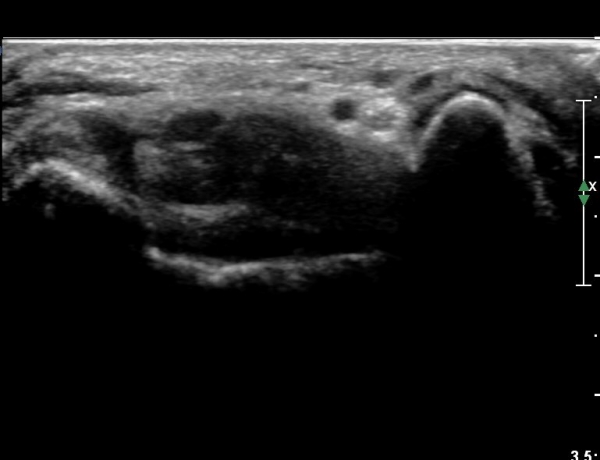

4 sono.jpg

¼Õ¹Ù´Ú ºÎÀ§¿¡¼­ ô°ñ½Å°æ ½ÉºÎ °¡Áö º´Áõ

(periphral neuropathy  of  deep palmar branch of ulnar nerve at palm level).